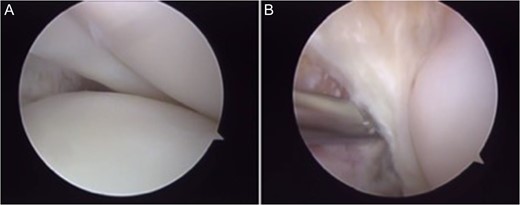

Final arthroscopic surgery image of the ACL and PCL reconstruction with the grafts tense and well positioned.

Radiographic image in AP (A) and lateral view (B) of left knee after surgery.

Patient was instructed to avoid weight bearing over the operated limb with a pair of crutches and use a non-hinged brace for 6 weeks after surgery, as well as to start physical therapy for muscle activation, patellar mobilization and range of motion gain. The patient was cleared for partial weight bearing at week 4 and full weight bearing at 8 weeks after the procedure. Six months after the surgery the patient reached 0°–120° of range of motion; tested negative on the Posterior Drawer, Pivot Shift, Appley and McMurray tests and grade 1+/4+ with firm endpoint on the Lachman and Anterior Drawer tests. He felt more stable when walking; was able to run and ride a bike. He chose not to return to contact sports to avoid further injuries. He continues to be monitored.